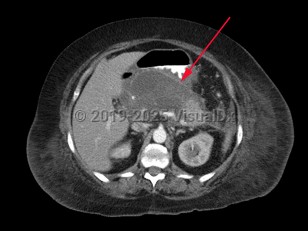

Pancreatic pseudocyst

A pancreatic pseudocyst is a localized, mature, fluid-filled collection, sometimes with debris, located outside of the pancreas. It has a nonepithelialized wall of fibrous and granulation tissue, with no necrosis present. Pancreatic pseudocysts typically appear at least 4 weeks after an episode of acute pancreatitis or blunt or penetrating pancreatic trauma. Pancreatic pseudocysts can also form in patients with chronic pancreatitis if there is an acute exacerbation of the underlying pancreatitis. Ten percent of patients with chronic pancreatitis will develop pseudocysts. Pancreatic pseudocysts are more commonly diagnosed in males.

Complications may include duodenal obstruction or biliary obstruction due to pseudocyst expansion, fistula formation into adjacent viscera including the peritoneal, pericardial, and pleural cavities, spontaneous pseudocyst infection, and pseudoaneurysm.